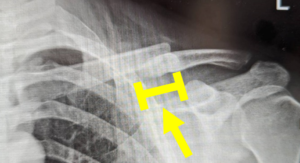

写真:癒合後=変形癒合(赤矢印) 短縮を伴う骨癒合であることが伺える(黄矢印)、患者より提供